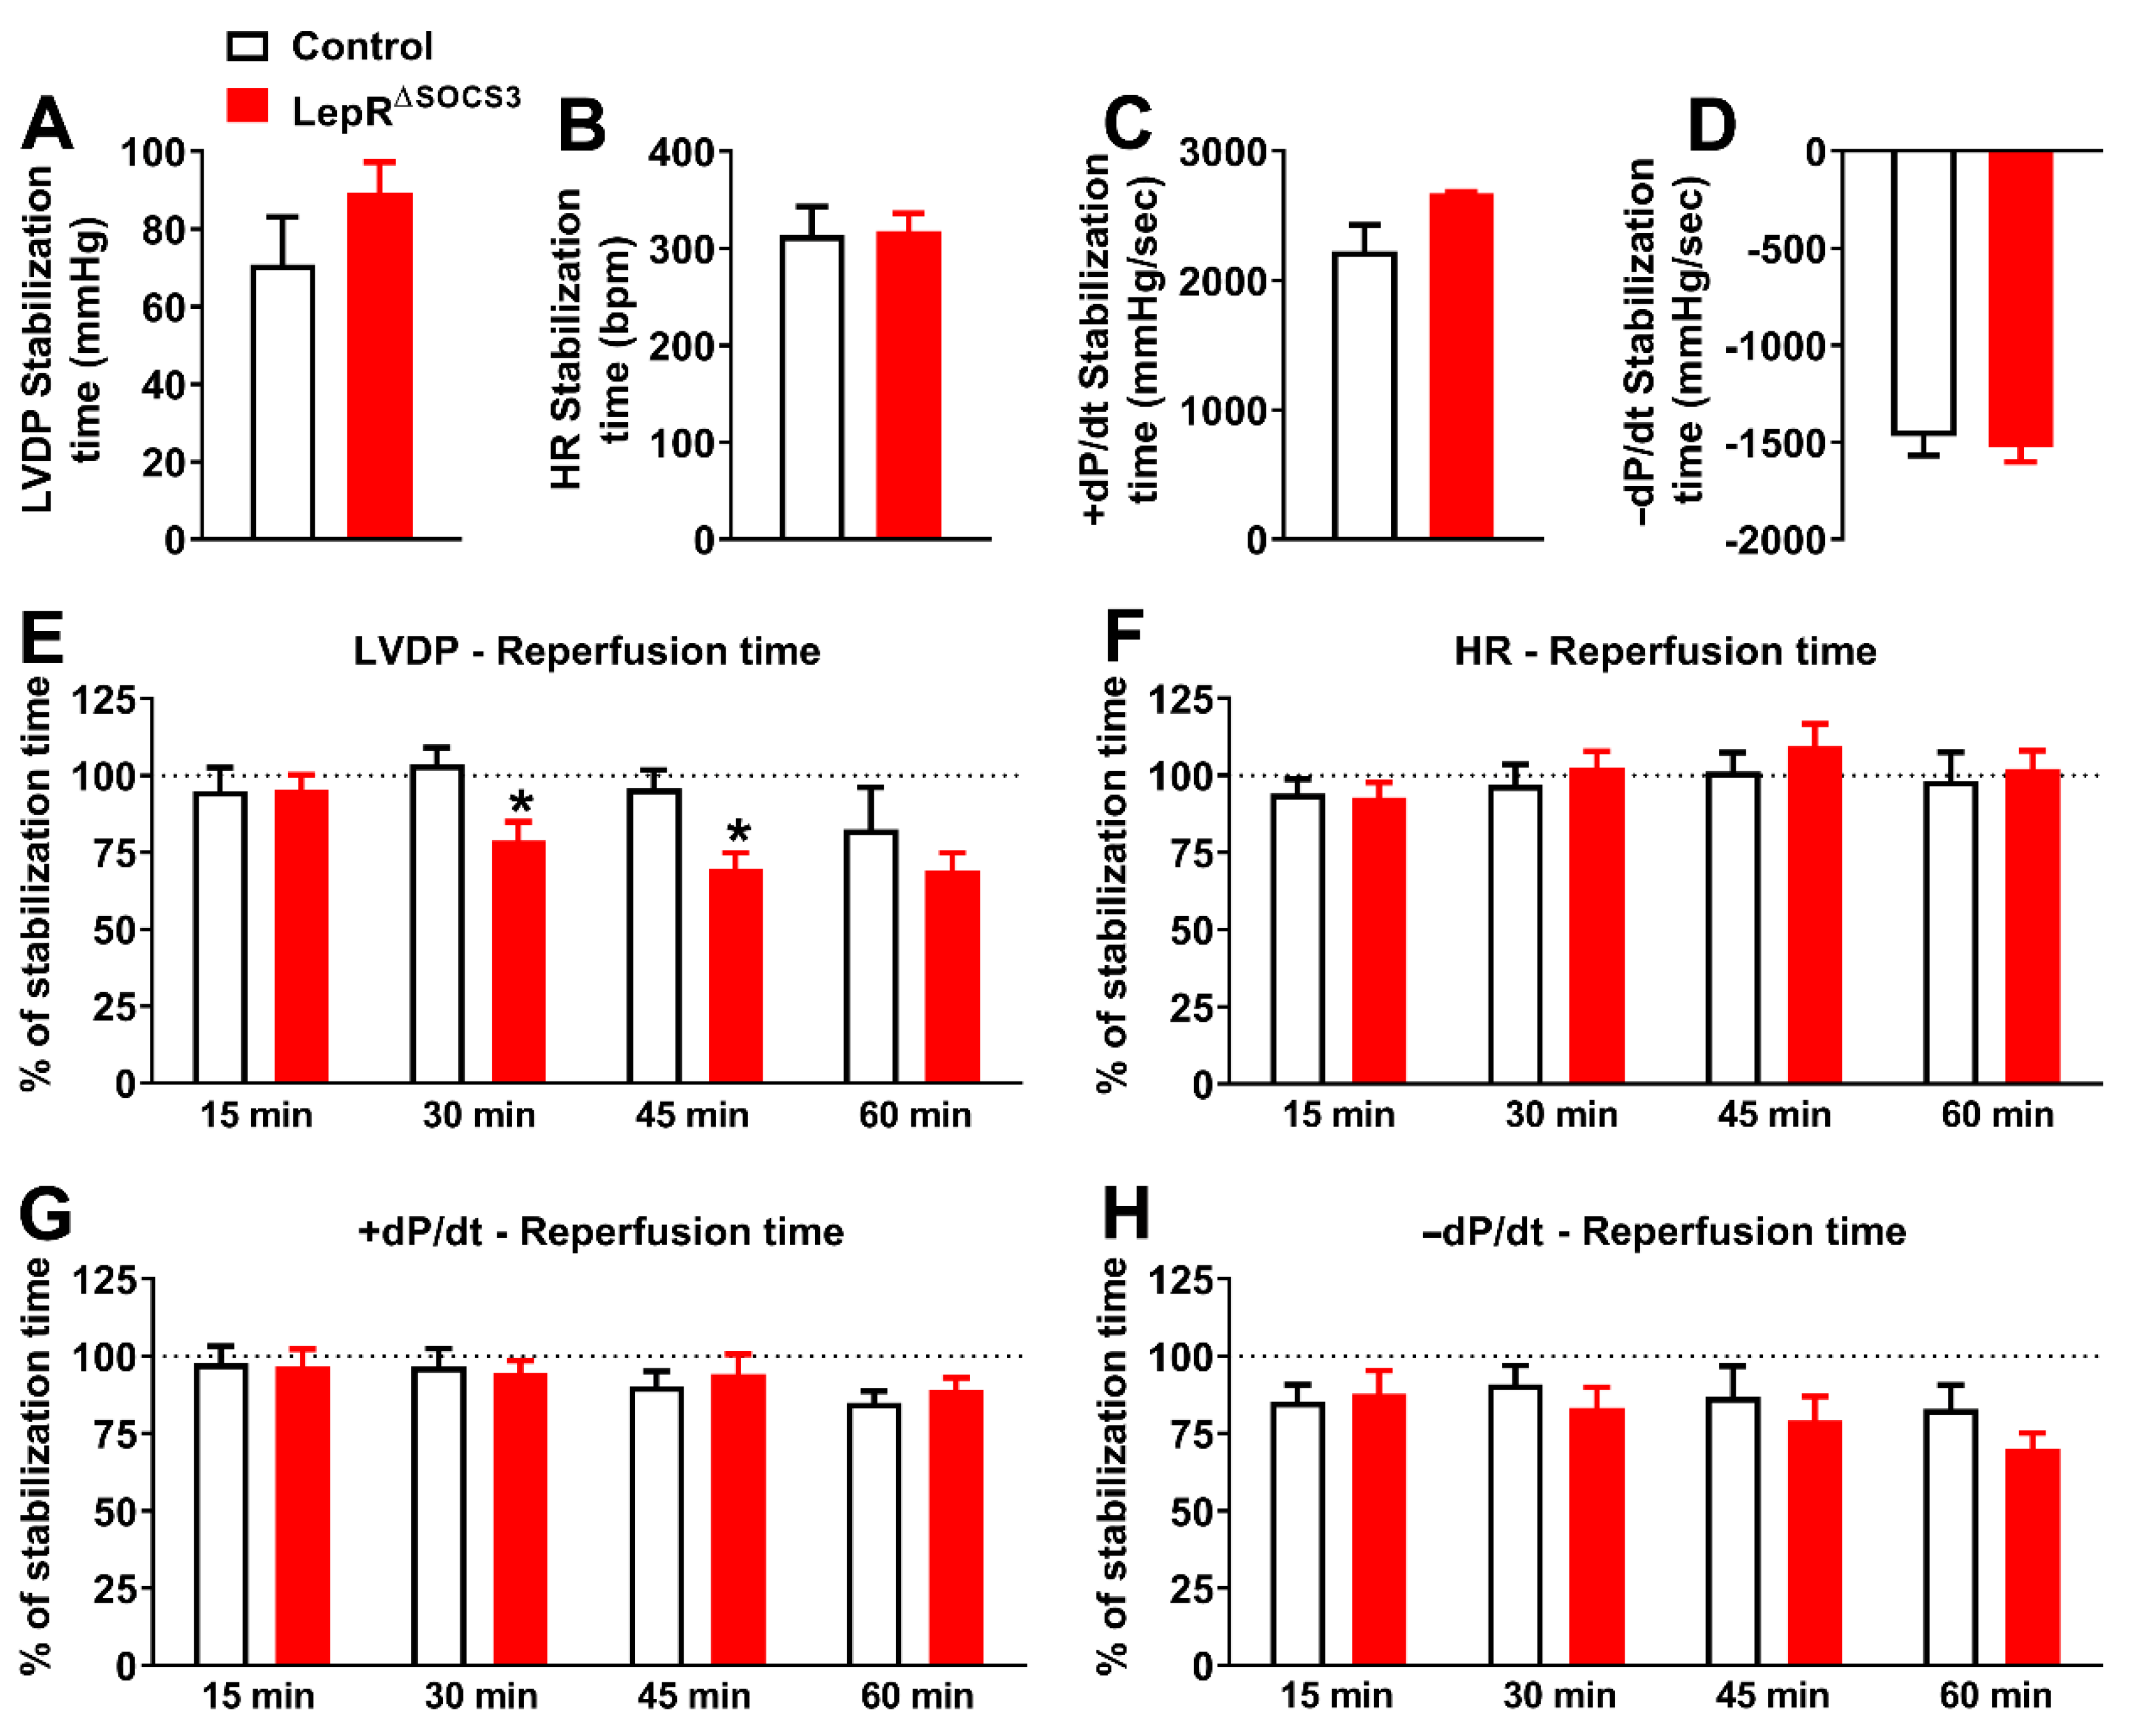

2.3. Cardiac Abnormalities and Decreased Survival Rate in Aging LepR∆SOCS3 Mice

4.6. Constant Flow Langendorff Preparation